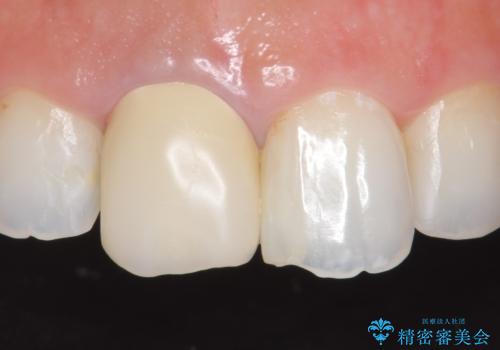

- 右上1の前歯の見た目が気になるので被せ物をやり替えたいといらっしゃった方の症例です。

再根管治療終了後、オールセラミッククラウン(スペシャル)によって隣在歯に合わせた補綴を行いました。

前歯の補綴ではオールセラミッククラウンを希望される患者様が多いですが、オールセラミッククラウンの中でも、エコノミー、スタンダード、スペシャル、エクセレントとランクがあります。

その中でも特に審美性が高いのがスペシャル、エクセレントです。スペシャル、エクセレントは口腔内写真をもとに熟練の技工士が、患者様の口腔内に合わせたオーダーメイドのクラウンを製作致します。